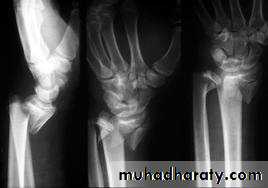

SMITH’S FRACTURE

Smith described a similar fracture about 20 years later. However, in this injury the distal fragment is displaced anteriorly (which is why it is sometimes called a ‘reversed Colles’),It is caused by a fall on the back of the hand.

The patient presents with a wrist injury, but there is no dinner-fork deformity. Instead, there is a ‘garden spade’ deformity.X-ray

There is a fracture through the distal radial metaphysis; a lateral view shows that the distalfragment is displaced and tilted anteriorly – the

opposite of a Colles’ fracture.

Treatment

The fracture is reduced by traction, supination and extension of the wrist, and the forearm is immobilized in a cast for 6 weeks. X-rays should be taken at 7–10 days to ensure the fracture has not slipped. Unstable fractures should be fixed with percutaneous wires or aplate.